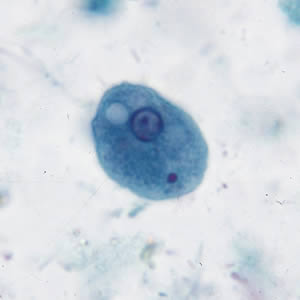

E. histolytica trophozoite

single nucleus with centrally placed karyosome. Cytoplasm contains ingested RBC’s.